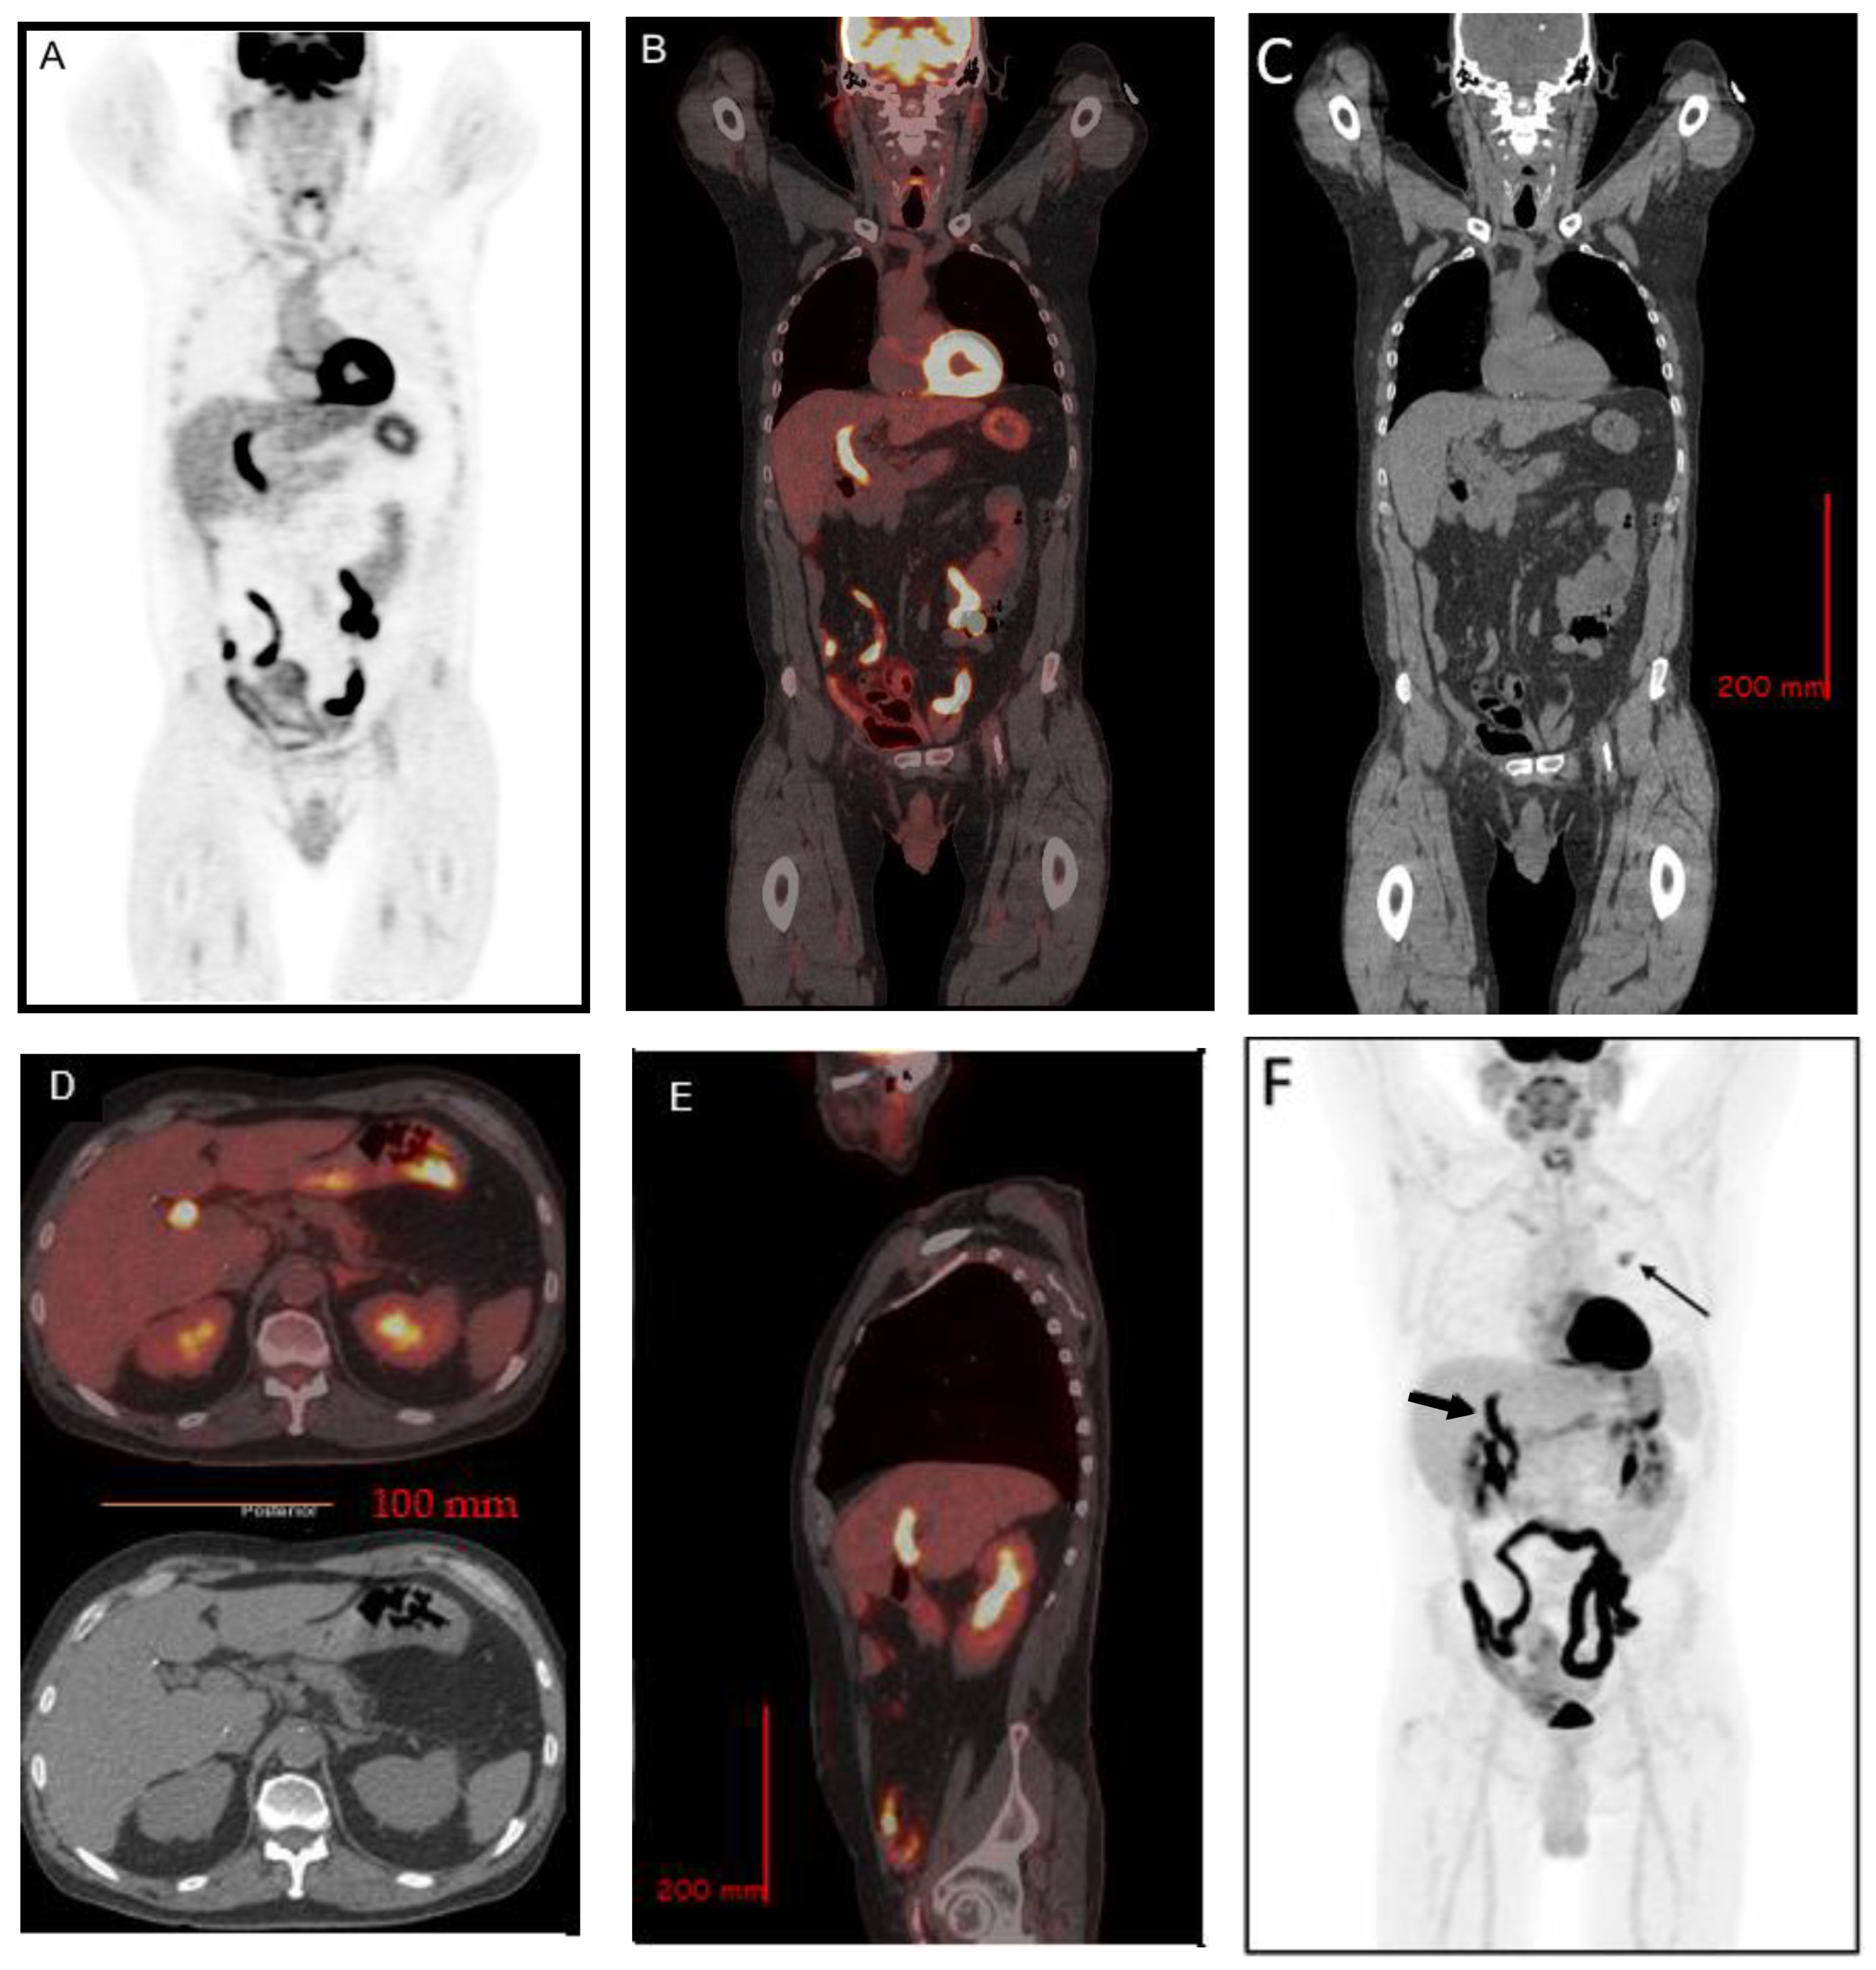

2. Case Report